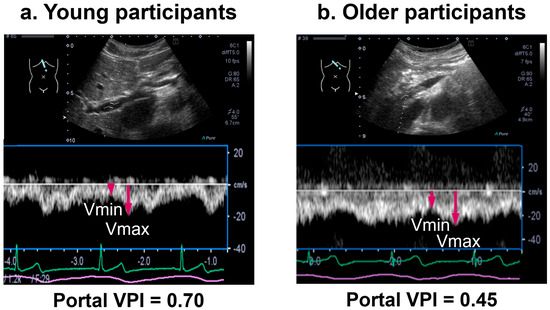

Portal venous (PV) flow Doppler velocimetry assesses venous congestion in heart failure, showing PV pulsatility due to backward transmission of right atrial pressure (RAP) through the sinusoids. However, PV pulsatility has also been observed under physiological conditions. We aimed to elucidate the mechanisms and contributing factors of PV pulsatility in healthy adults. Pulsed-wave Doppler recordings of the hepatic venous (HV) and PV flow were obtained with electrocardiography. A- and V-wave velocities and their timings relative to the P- and R-waves (P-HVA, R-HVV) were measured from the HV waveforms. From PV waveforms, atrial and ventricular systolic descent flow velocities and their timings (P-PVA, R-PVV) were measured. The PV pulsatility index (VPI) was calculated. There were no differences between P-PVA and P-HVA, and between R-PVV and R-HVV, indicating similar waveforms. Seventy-nine percent of participants showed a VPI ≥ 0.3, with a higher VPI in younger vs. older participants (0.7 vs. 0.3, p < 0.01). Only age was independently associated with VPI (β = −0.56, p < 0.01). PV pulsatility was common in healthy adults, suggesting RAP transmission via the sinusoids; this physiological phenomenon was attenuated with aging. These findings highlight the importance of considering age-related physiological changes when interpreting the PV flow. Full article